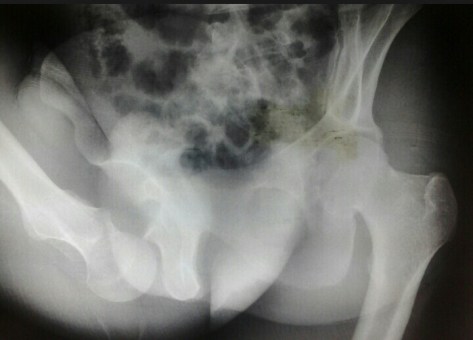

Keadaan saat awal operasi (durante op) bagian ujung kaki (distal) tampak berwarna pucat kebiruan. Tidak dijumpai perdarahan aktif. Hematom ada diantara jaringan bawah kulit (subkutis), diantara otot yang tercabik-cabik. Dilakukan tindakan meluruskan kembali tulang, re-aligment sekaligus dilakukan debridemen. Posisi tulang yang pecah fragmented dilakukan re-aligment. Selanjutnya dilakukan fiksasi tulang (external fixation). Penutupan jaringan lunak (soft tissue) dilakukan sedapatnya dengan tarikan regang yang sedikit (minimal tension). Diakhir operasi ujung kaki mulai tampak kemerahan kembali.

Patah tulang tibia (tibial fracture) adalah patah tulang panjang yang paling sering dijumpai khususnya pada bagian batang tulang shaft (plateau, shaft dan plafon). Dari mekanismenya dibedakan menjadi 2 jenis yaitu low energy fracture pattern dan high energy fracture pattern.

Dari mekanisme low energy umumnya didapatkan alibat cidera tidak langsung (torsional injury) dengan ciri khas didapatkan patah tulang fibula pada level yang berbeda, sedangkan untuk mekanisme high energy injury umumnya dari benturan langsung yang seringkali berupa patahan dengan bentuk baji (wedge) atau short oblique dengan bagian yang terpecah (kominutif fragment).